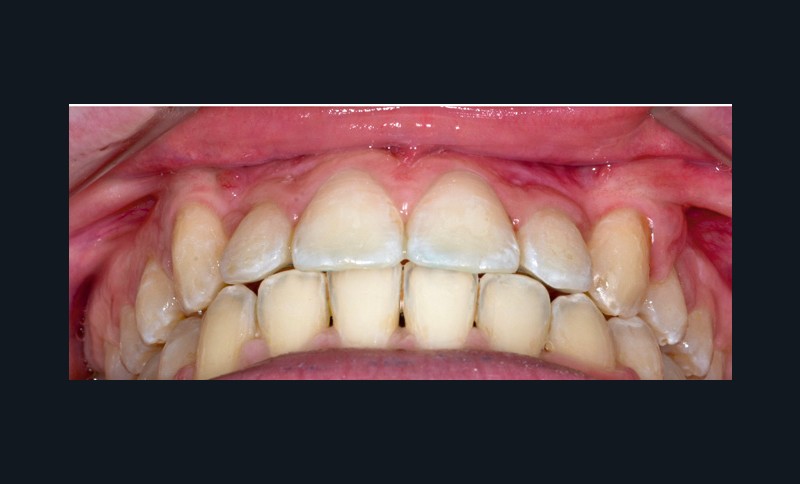

L’appareil est déposé après la mise en place de contentions collées de 12 à 22 et de 33 à 43 avec le port nocturne d’une plaque de Hawley à l’arcade maxillaire. Le temps de traitement actif a été de 41 mois.

Les traitements des transpositions sont souvent complexes car il y a plusieurs facteurs à prendre en compte : la morphologie dentaire, les considérations esthétiques, le stade d’édification radiculaire, la position des couronnes et des racines dans le processus alvéolaire dans les trois plans de l’espace, le temps de traitement et la motivation du patient [1]. L’utilisation d’un renfort d’ancrage transpalatin pour la correction des transpositions de canines est bien documentée dans la littérature [2], d’autant plus que chez ces jeunes patients, idéalement traités avant l’âge de 10 ans [3], la pose d’ancrages osseux en vestibulaire est contre-indiquée au vu de la présence de germes au niveau des sites d’insertions. Le choix d’un dispositif à mémoire de forme, préactivé pour délivrer des forces légères et continues (300-500 g) favorisant l’expansion transversale et la dérotation molaire simultanée sans réactivation manuelle, associé à l’utilisation de bras en TMA reliant les molaires aux canines incluses, nous a permis de profiter du moment généré par la dérotation des 16 et 26 pour emmener les canines en direction vestibulaire. Nous avons ainsi pu préserver les racines des incisives maxillaires lors de la correction des transpositions, de manière simple, contrôlée et confortable pour la patiente, tout en facilitant la phase de multi-attache qui a suivi.